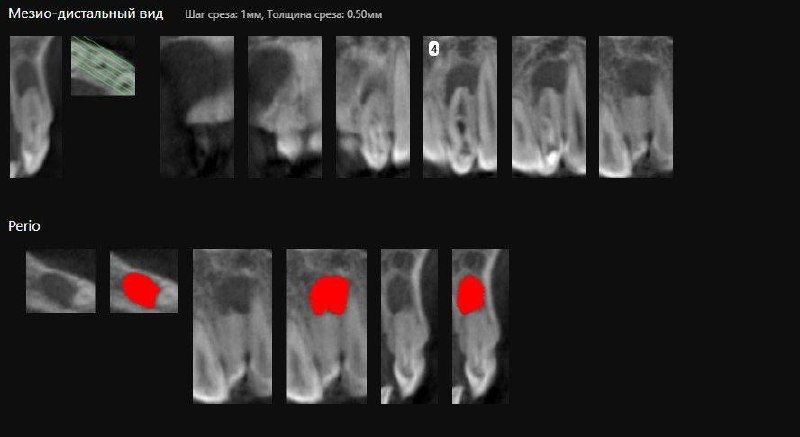

🦷 Π›Π•Π§Π•ΠΠ˜Π• DENS IN CERVICIS (DENS INVAGINATUS) Как Π²Ρ‹ ΠΏΠΎΠΌΠ½ΠΈΡ‚Π΅, Ρ€Π°Π½Π΅Π΅ я ΡƒΠΆΠ΅ рассказывала ΠΎ Ρ‚Π°ΠΊΠΎΠΌ интСрСсном Π΄ΠΈΠ°Π³Π½ΠΎΠ·Π΅, ΠΊΠ°ΠΊ dens invaginatus ΠΈΠ»ΠΈ Β«Π±Π΅Ρ€Π΅ΠΌΠ΅Π½Π½Ρ‹ΠΉ Π·ΡƒΠ±Β». БСгодня Ρ…ΠΎΡ‡Ρƒ ΠΏΠΎΠ΄Π΅Π»ΠΈΡ‚ΡŒΡΡ клиничСским случаСм лСчСния 2.2 Π·ΡƒΠ±Π° с Π΄Π°Π½Π½ΠΎΠΉ Π°Π½ΠΎΠΌΠ°Π»ΠΈΠ΅ΠΉ развития. πŸ”Ή Π”ΠΈΠ°Π³Π½ΠΎΠ·: Dens invaginatus (Ρ‚ΠΈΠΏ I ΠΏΠΎ классификации Oehlers) πŸ”Ή Π’Π°ΠΊΡ‚ΠΈΠΊΠ°: ΠšΠΎΠ½ΡΠ΅Ρ€Π²Π°Ρ‚ΠΈΠ²Π½ΠΎΠ΅ Π»Π΅Ρ‡Π΅Π½ΠΈΠ΅ ΠΏΠΎ стандарту β€” Π² Π΄Π²Π° посСщСния. ΠŸΠ΅Ρ€Π²ΠΎΠ΅ посСщСниС: - Π€ΠΎΡ€ΠΌΠΈΡ€ΠΎΠ²Π°Π½ΠΈΠ΅ доступа ΠΊ ΠΊΠΎΡ€Π½Π΅Π²Ρ‹ΠΌ ΠΊΠ°Π½Π°Π»Π°ΠΌ - ΠœΠ΅Ρ…Π°Π½ΠΈΡ‡Π΅ΡΠΊΠ°Ρ ΠΈ мСдикамСнтозная ΠΎΠ±Ρ€Π°Π±ΠΎΡ‚ΠΊΠ° ΠΊΠ°Π½Π°Π»ΠΎΠ² - Π’Ρ€Π΅ΠΌΠ΅Π½Π½ΠΎΠ΅ ΠΏΠ»ΠΎΠΌΠ±ΠΈΡ€ΠΎΠ²Π°Π½ΠΈΠ΅ Π³ΠΈΠ΄Ρ€ΠΎΠΎΠΊΠΈΡΡŒΡŽ ΠΊΠ°Π»ΡŒΡ†ΠΈΡ Π’Ρ‚ΠΎΡ€ΠΎΠ΅ посСщСниС: - Π£Π΄Π°Π»Π΅Π½ΠΈΠ΅ Π²Ρ€Π΅ΠΌΠ΅Π½Π½ΠΎΠΉ пасты - ΠžΠΊΠΎΠ½Ρ‡Π°Ρ‚Π΅Π»ΡŒΠ½ΠΎΠ΅ ΠΏΠ»ΠΎΠΌΠ±ΠΈΡ€ΠΎΠ²Π°Π½ΠΈΠ΅ ΠΊΠΎΡ€Π½Π΅Π²ΠΎΠ³ΠΎ ΠΊΠ°Π½Π°Π»Π° биокСрамичСским силСром - ВосстановлСниС ΠΊΠΎΡ€ΠΎΠ½ΠΊΠΎΠ²ΠΎΠΉ части Π·ΡƒΠ±Π° свСтоотвСрТдаСмым ΠΊΠΎΠΌΠΏΠΎΠ·ΠΈΡ‚ΠΎΠΌ с ΠΏΡ€ΠΈΠΌΠ΅Π½Π΅Π½ΠΈΠ΅ΠΌ Ρ‚Π΅Ρ…Π½ΠΎΠ»ΠΎΠ³ΠΈΠΈ армирования Ribbond 🎯 Π’Π°ΠΊΡ‚ΠΈΠΊΠ° Π²Ρ‹Π±Ρ€Π°Π½Π° с ΡƒΡ‡Π΅Ρ‚ΠΎΠΌ анатомичСских особСнностСй Π·ΡƒΠ±Π° ΠΈ ΠΏΡ€ΠΎΡ„ΠΈΠ»Π°ΠΊΡ‚ΠΈΠΊΠΈ Π²ΠΎΠ·ΠΌΠΎΠΆΠ½Ρ‹Ρ… ослоТнСний. ΠžΡ‡Π΅Π½ΡŒ Π²Π°ΠΆΠ½ΠΎ Π½Π° этапС диагностики ΠΏΡ€Π°Π²ΠΈΠ»ΡŒΠ½ΠΎ ΠΎΡ†Π΅Π½ΠΈΡ‚ΡŒ Π³Π»ΡƒΠ±ΠΈΠ½Ρƒ ΠΈΠ½Π²Π°Π³ΠΈΠ½Π°Ρ†ΠΈΠΈ ΠΈ риск ΠΏΠ΅Ρ€Ρ„ΠΎΡ€Π°Ρ†ΠΈΠΈ! πŸ“£ КоллСги, Π΄Π΅Π»ΠΈΡ‚Π΅ΡΡŒ Π² коммСнтариях: Ρƒ ΠΊ

Как Π²Ρ‹ ΠΏΠΎΠΌΠ½ΠΈΡ‚Π΅, Ρ€Π°Π½Π΅Π΅ я ΡƒΠΆΠ΅ рассказывала ΠΎ Ρ‚Π°ΠΊΠΎΠΌ интСрСсном Π΄ΠΈΠ°Π³Π½ΠΎΠ·Π΅, ΠΊΠ°ΠΊ dens invaginatus ΠΈΠ»ΠΈ Β«Π±Π΅Ρ€Π΅ΠΌΠ΅Π½Π½Ρ‹ΠΉ Π·ΡƒΠ±Β».

БСгодня Ρ…ΠΎΡ‡Ρƒ ΠΏΠΎΠ΄Π΅Π»ΠΈΡ‚ΡŒΡΡ клиничСским случаСм лСчСния 2.2 Π·ΡƒΠ±Π° с Π΄Π°Π½Π½ΠΎΠΉ Π°Π½ΠΎΠΌΠ°Π»ΠΈΠ΅ΠΉ развития.

πŸ”Ή Π”ΠΈΠ°Π³Π½ΠΎΠ·: Dens invaginatus (Ρ‚ΠΈΠΏ I ΠΏΠΎ классификации Oehlers)

πŸ”Ή Π’Π°ΠΊΡ‚ΠΈΠΊΠ°: ΠšΠΎΠ½ΡΠ΅Ρ€Π²Π°Ρ‚ΠΈΠ²Π½ΠΎΠ΅ Π»Π΅Ρ‡Π΅Π½ΠΈΠ΅ ΠΏΠΎ стандарту β€” Π² Π΄Π²Π° посСщСния.

ΠŸΠ΅Ρ€Π²ΠΎΠ΅ посСщСниС:

- Π€ΠΎΡ€ΠΌΠΈΡ€ΠΎΠ²Π°Π½ΠΈΠ΅ доступа ΠΊ ΠΊΠΎΡ€Π½Π΅Π²Ρ‹ΠΌ ΠΊΠ°Π½Π°Π»Π°ΠΌ

- ΠœΠ΅Ρ…Π°Π½ΠΈΡ‡Π΅ΡΠΊΠ°Ρ ΠΈ мСдикамСнтозная ΠΎΠ±Ρ€Π°Π±ΠΎΡ‚ΠΊΠ° ΠΊΠ°Π½Π°Π»ΠΎΠ²

- Π’Ρ€Π΅ΠΌΠ΅Π½Π½ΠΎΠ΅ ΠΏΠ»ΠΎΠΌΠ±ΠΈΡ€ΠΎΠ²Π°Π½ΠΈΠ΅ Π³ΠΈΠ΄Ρ€ΠΎΠΎΠΊΠΈΡΡŒΡŽ ΠΊΠ°Π»ΡŒΡ†ΠΈΡ

Π’Ρ‚ΠΎΡ€ΠΎΠ΅ посСщСниС:

- Π£Π΄Π°Π»Π΅Π½ΠΈΠ΅ Π²Ρ€Π΅ΠΌΠ΅Π½Π½ΠΎΠΉ пасты

- ΠžΠΊΠΎΠ½Ρ‡Π°Ρ‚Π΅Π»ΡŒΠ½ΠΎΠ΅ ΠΏΠ»ΠΎΠΌΠ±ΠΈΡ€ΠΎΠ²Π°Π½ΠΈΠ΅ ΠΊΠΎΡ€Π½Π΅Π²ΠΎΠ³ΠΎ ΠΊΠ°Π½Π°Π»Π° биокСрамичСским силСром

- ВосстановлСниС ΠΊΠΎΡ€ΠΎΠ½ΠΊΠΎΠ²ΠΎΠΉ части Π·ΡƒΠ±Π° свСтоотвСрТдаСмым ΠΊΠΎΠΌΠΏΠΎΠ·ΠΈΡ‚ΠΎΠΌ с ΠΏΡ€ΠΈΠΌΠ΅Π½Π΅Π½ΠΈΠ΅ΠΌ Ρ‚Π΅Ρ…Π½ΠΎΠ»ΠΎΠ³ΠΈΠΈ армирования Ribbond

🎯 Π’Π°ΠΊΡ‚ΠΈΠΊΠ° Π²Ρ‹Π±Ρ€Π°Π½Π° с ΡƒΡ‡Π΅Ρ‚ΠΎΠΌ анатомичСских особСнностСй Π·ΡƒΠ±Π° ΠΈ ΠΏΡ€ΠΎΡ„ΠΈΠ»Π°ΠΊΡ‚ΠΈΠΊΠΈ Π²ΠΎΠ·ΠΌΠΎΠΆΠ½Ρ‹Ρ… ослоТнСний. ΠžΡ‡Π΅Π½ΡŒ Π²Π°ΠΆΠ½ΠΎ Π½Π° этапС диагностики ΠΏΡ€Π°Π²ΠΈΠ»ΡŒΠ½ΠΎ ΠΎΡ†Π΅Π½ΠΈΡ‚ΡŒ Π³Π»ΡƒΠ±ΠΈΠ½Ρƒ ΠΈΠ½Π²Π°Π³ΠΈΠ½Π°Ρ†ΠΈΠΈ ΠΈ риск ΠΏΠ΅Ρ€Ρ„ΠΎΡ€Π°Ρ†ΠΈΠΈ!